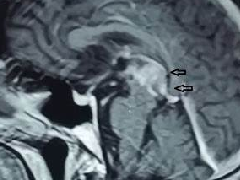

术中磁共振成像辅助全切脊髓内

近年来快速的技术进步对神经外科学产生了影响。手术室中...